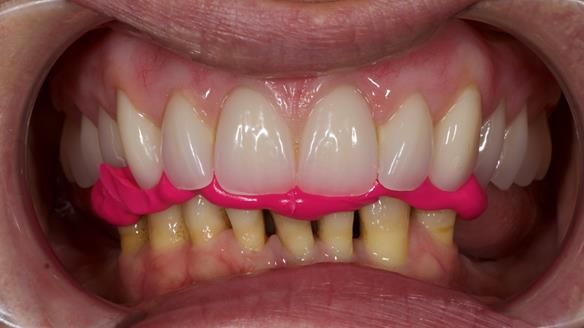

We provided her with an immediate upper denture (Mk 1), followed by a definitive metal-based upper denture (Mk 2). A lower removable partial denture was discussed, to be made only if needed once the upper treatment was complete. However, at review, this wasn’t necessary — Adnana had excellent neuromuscular control and function, even with a shortened dental arch (SDA).

- Definitive denture (Mk 2), metal-based and custom-designed for her face

- A restored smile, restored lip support, and a patient who owned the journey